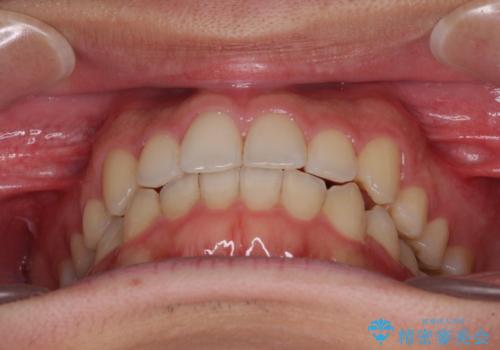

狭い歯列と前歯のデコボコ インビザラインによる矯正治療

- 上下前歯のデコボコを気にして来院された患者様です。

インビザラインによる上下歯列の拡大と、IPR(歯と歯の間を削る)にるスペースの獲得により、前歯のデコボコと狭い歯列を改善することとしました。

比較的軽度な歯列不正であったため、治療期間はそれほど長くはならないと予想されました。

しかしながら、あまりしっかりとマウスピースを装着していなかったため、思いの外期間が長引いてしまいました。

また、仕上がりの歯列にも若干の叢生が残ってしまいました。